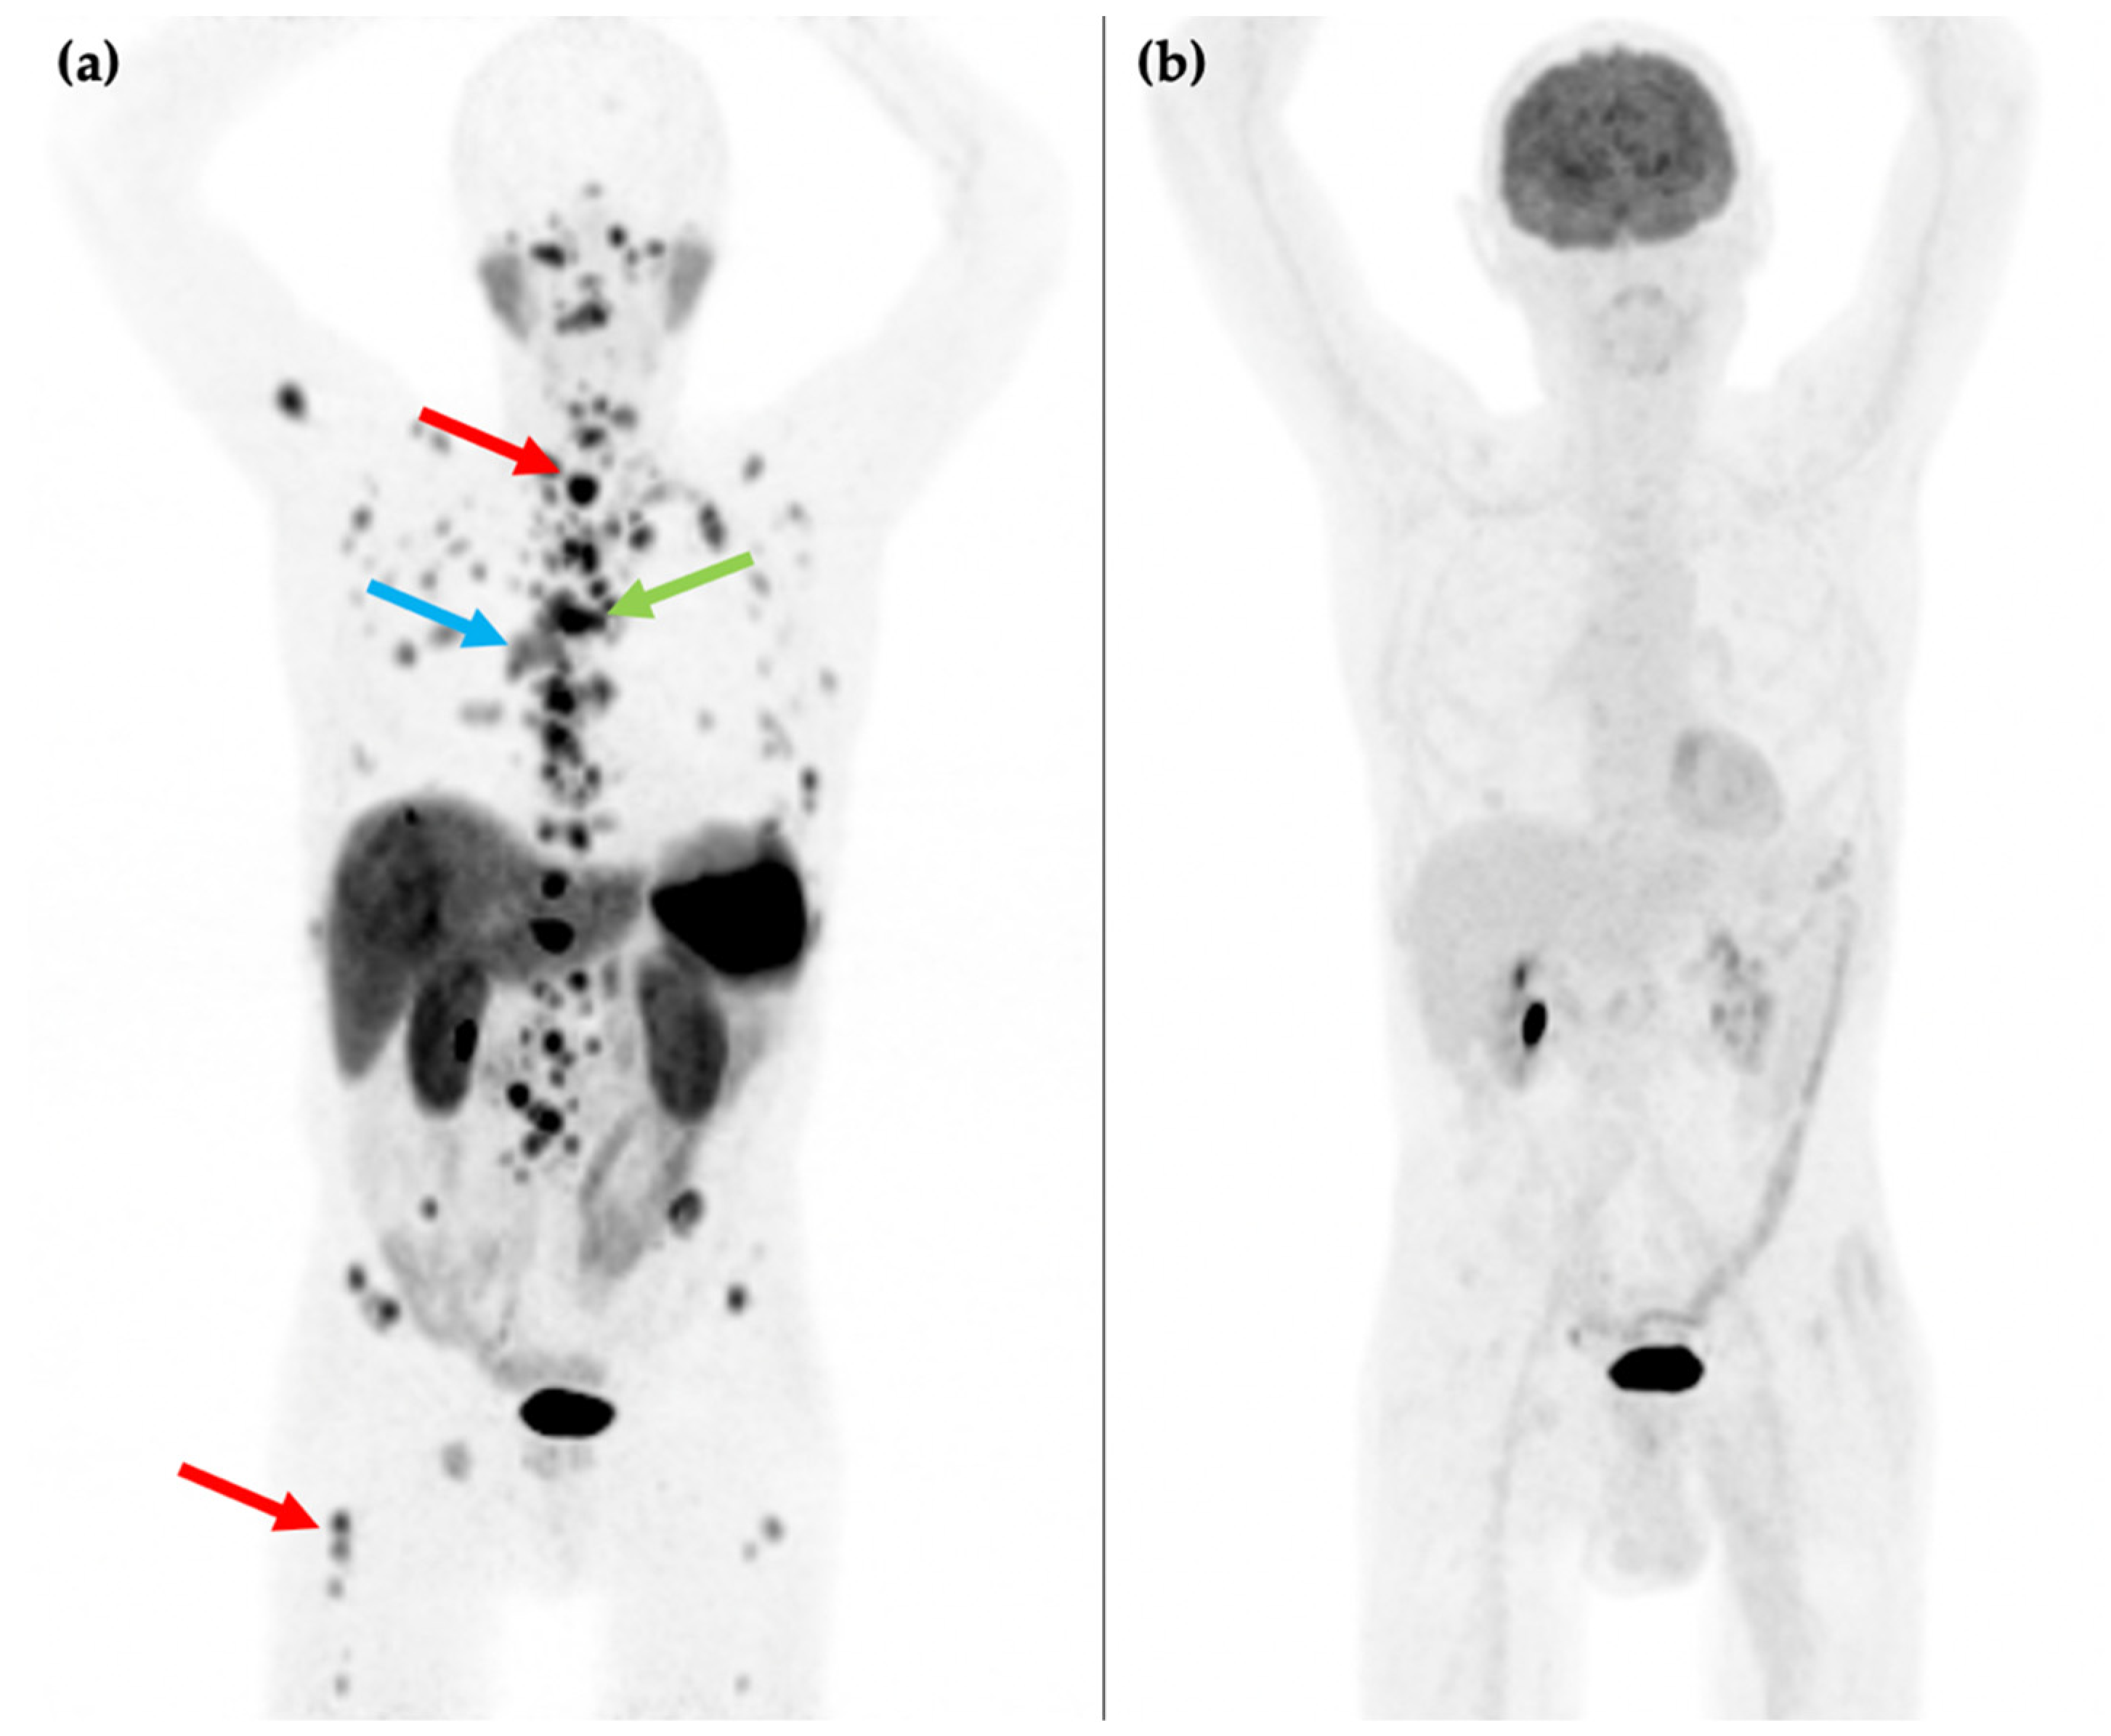

F-18 fluorodeoxyglucose (18F-FDG) PET has a role in imaging of high-grade NEN because of lower SSTR expression in these tumors [37,38]. As a glucose analogue, FDG uptake is proportional to metabolic activity and is associated with cellular proliferation. This corresponds to reduced survival and aggressive tumor behavior including a higher Ki-67 index [39,40]. It is thought to have little to no impact on treatment decisions for G1 NENs, as these exhibit no or minimal metabolic activity (Figure 2), and moderate impact on G2 NENs [41]. Consequently, its routine use is indicated in clinical guidelines [42] for high grade G2 and G3 tumors only [43,44]. It has been suggested that G2 tumors with a Ki-67 of over 10% should be imaged with 18F-FDG [45]. Although recent studies have assessed the value of combining 18F-FDG and 68Ga-DOTA-peptide PET/CT to stratify patients at major risk of progression, the heterogenous patterns of uptake in the intermediate group between the two modalities makes it difficult to standardize treatment strategies [46] based on results obtained. A recent systematic review [47] has suggested combined use only in specific circumstances, for instance to characterize indeterminate G2 tumors, to assess disease if there is suspected progression following a period of prolonged stability, or if there is a discrepancy between conventional imaging and clinical/biochemical assessment.

Figure 2.

81-year-old male with an endobronchial lesion identified on conventional CT imaging. 68Ga-DOTATATE PET/CT MIP image (a) shows an SSTR positive right-sided bronchial lesion (blue arrow), mediastinal lymphadenopathy (green arrow), and innumerable bone metastases in the axial and proximal appendicular skeleton including in the spine and right femur (red arrows). 18F-FDG PET/CT MIP image (b) shows that the SSTR positive lesions are not FDG avid. Histology confirmed a G1 typical bronchial carcinoid (Ki-67 1–2%).